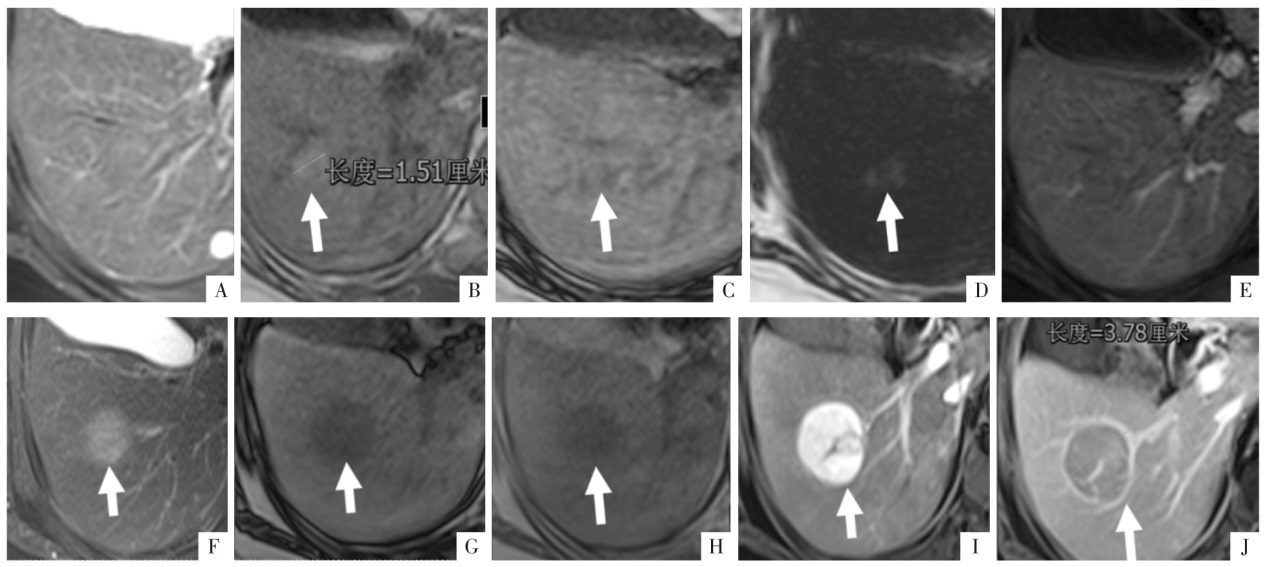

图9

病人女,67岁,慢性乙肝病史20余年,甲胎蛋白阴性,肝硬化背景中含有脂肪变性的结节(白箭),进展为肝细胞癌。A—D图分别为T

2

WI、T

1

WI同相位、反相位及脂像,同相位可见直径约1.5 cm脂肪变性结节,T

WI未见显示;E图为动脉期影像,未见强化。F—J图分别为3年后复查T

WI反相位、T

WI同相位、增强扫描动脉期及静脉期影像,显示病灶增大至3.8 cm,脂肪变性消失,可见非周边的动脉期高强化、廓清以及强化包膜征象,呈现典型肝细胞癌征象。